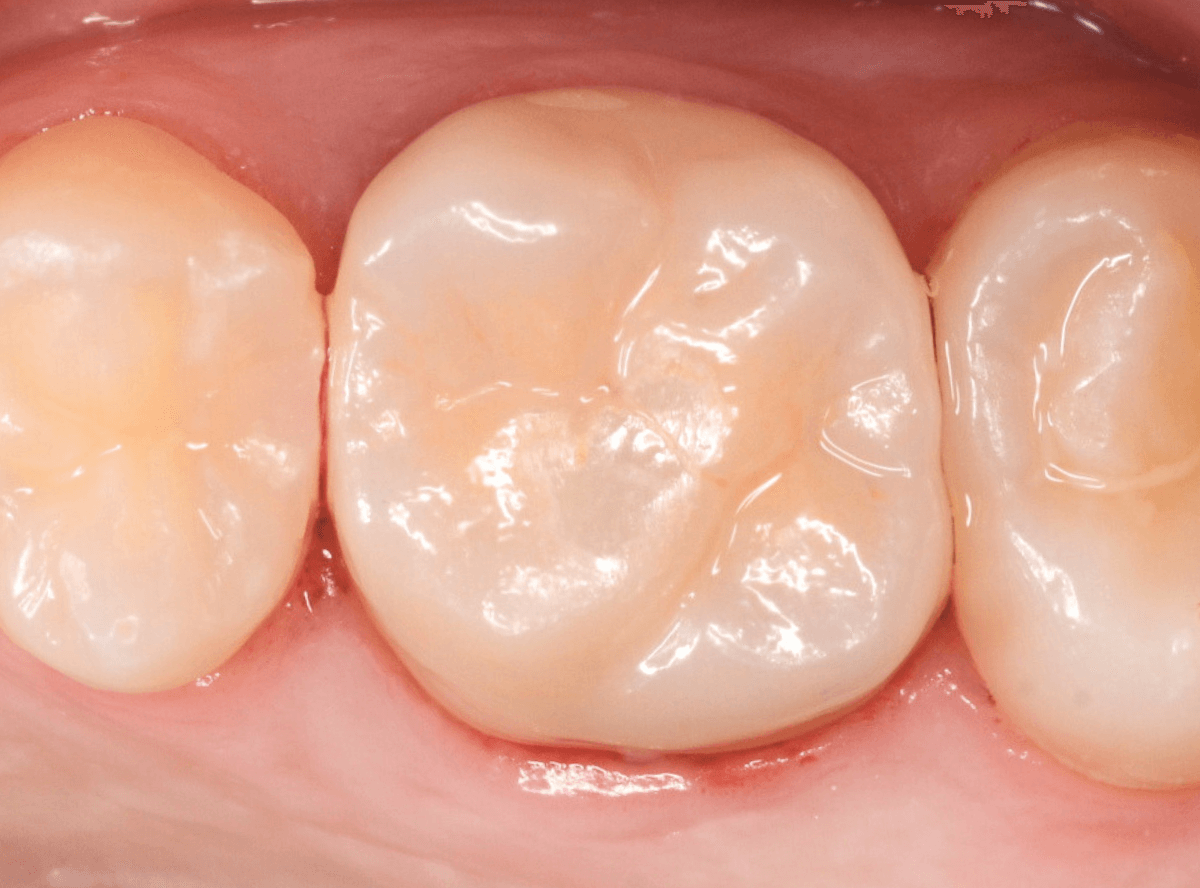

set後の写真です。

患者さんにも満足していただける仕上がりになりました。

治療前後の比較写真になります。